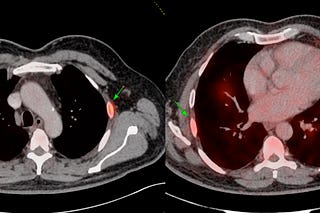

COD 148 - A Rib Lesion with Uptake on PET

44-years old with fever and a PET showing an osteolytic lesion with uptake in the left 7th rib.